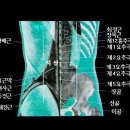

허리병 침구치료 ㅡ 1.요통 : 허리 부위에서 다리까지 광범위하게 나타나는 통증 신수-경문-대장수-차료 신주-심수-비수-곡지...부축받아 오신 분도 단번에 허리를 곧추 펴고 편하게 걷습니다. 침은 호침중에서 가장 가늘고 짧은 침이면 됩니다. 대장수...